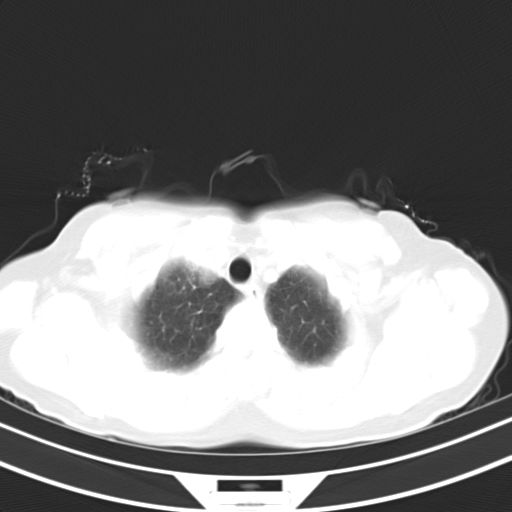

女,47岁,咳嗽胸痛一个星期,我们考虑肺结核,左下肺病灶肿瘤像不像,请高手指点。急。

右肺考虑炎症,建议抗炎后复查,左肺下叶考虑肺不张。

炎性灶;【1楔状实变影,有支气管气象,2近端纹理影增重】

右肺上叶前段积左肺舌叶炎症,建议严格抗炎后2周复查!

右肺上叶尖后段班片影不能出外肺结核。左肺舌叶三角形实变影,增强明显。考虑炎性病变